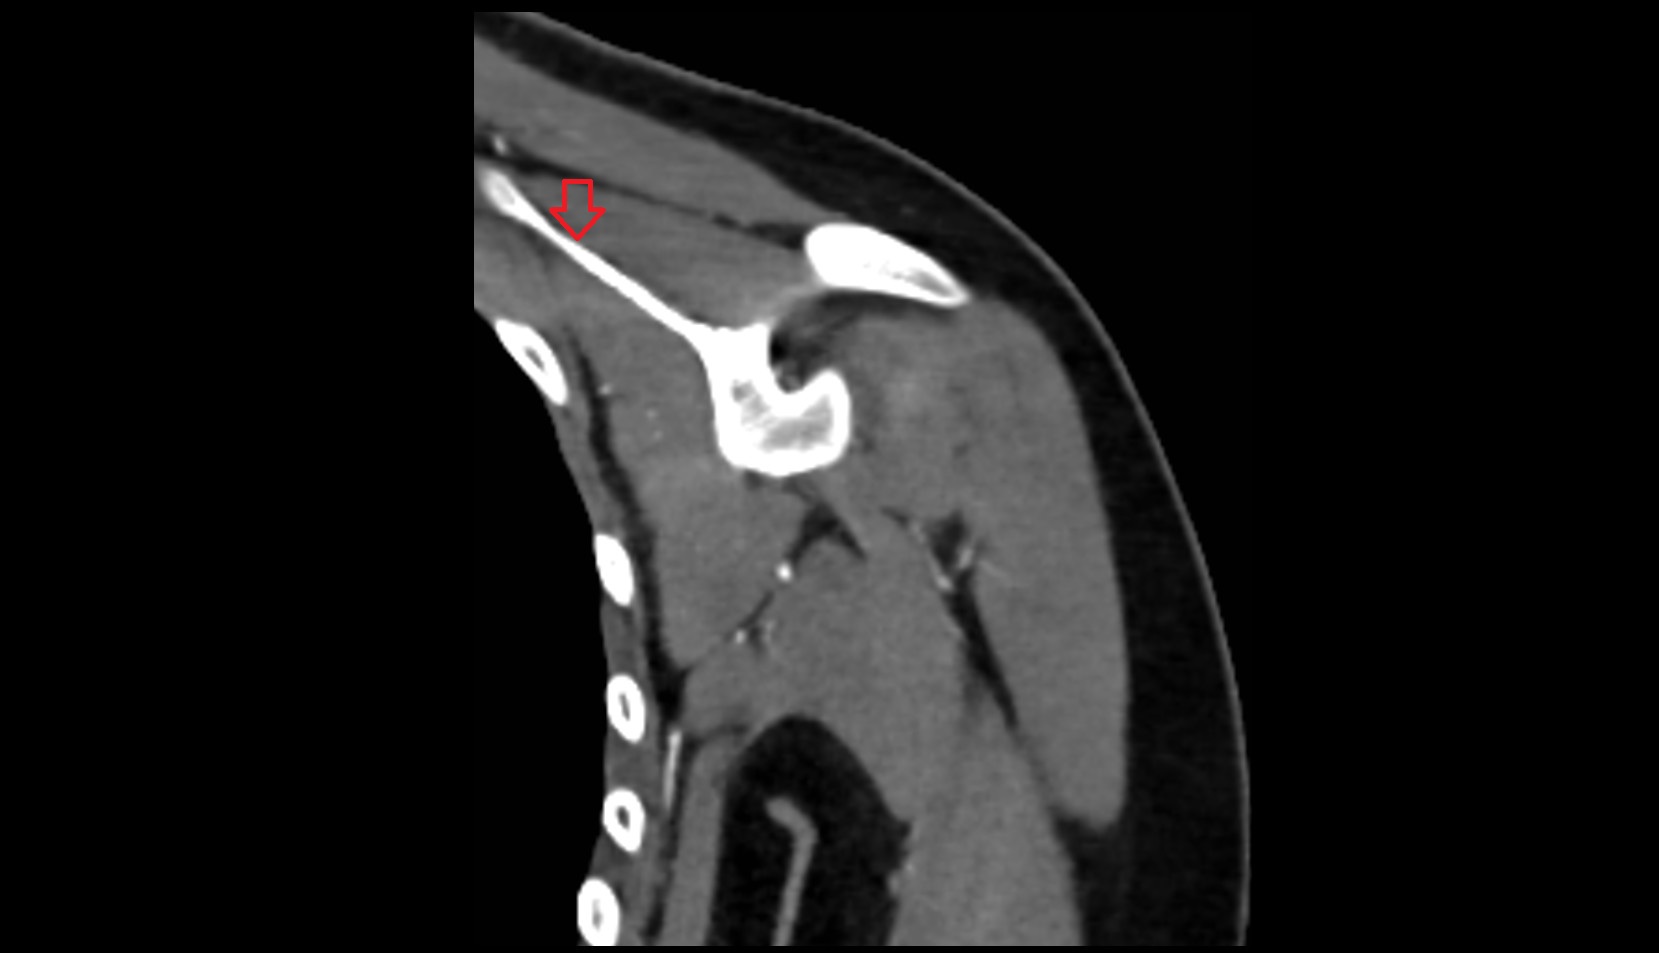

- Spine of scapula

- Acromion process of scapula

- Shaft (body) of clavicle

- Acromial end of clavicle

- Sternoclavicular joint